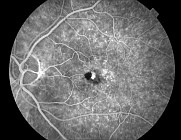

Fundus Fluorecein Angiography

Detailing Retinal Vessels

Diabetic Retinopathy |

Age-Related Macular Degeneration |

Central Retinal vein Occlusion |